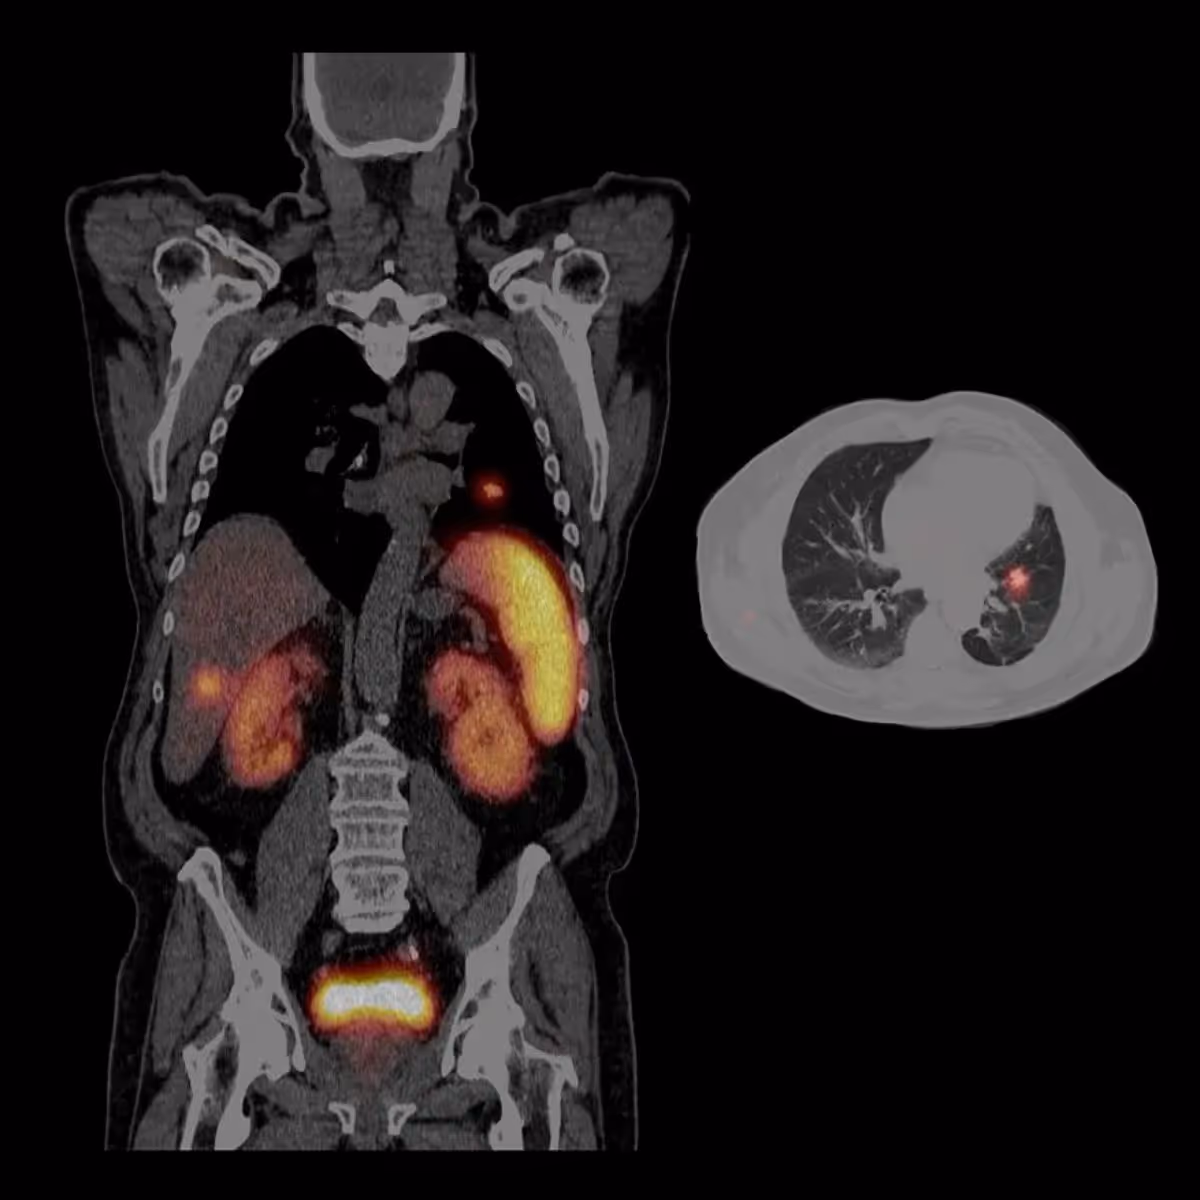

Symbia Intevo Spect Ct

NEUROENDOCRINE TUMOR METASTASES

(Image credit: www.siemens-healthineers.com)